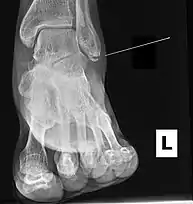

Psoriatic arthritis affecting the foot

Exact incidence rates are unknown, but it is believed that the Maisonneuve fracture accounts for 5% of all ankle injuries treated in surgery.[9][17] The Maisonneuve fracture has been reported in patients as young as 17–19 years old, and up to 42–70 years old.[7][9][11] The injury is mostly seen in male patients. A clinical article on studies conducted between 2014 and 2019, published in Orthopaedic Surgery in 2020, reported that 78% of admitted patients with a Maisonneuve fracture were male.[8]

Sporting injuries are the most common risk factor of causing a Maisonneuve fracture. Sport-related injuries were associated with 50% of all Maisonneuve fracture cases examined in one clinical study.[4] Comorbidity of the Maisonneuve fracture and other health conditions, such as hypertension, obesity, and psoriatic arthritis, have been identified in patient medical histories.[4][6]